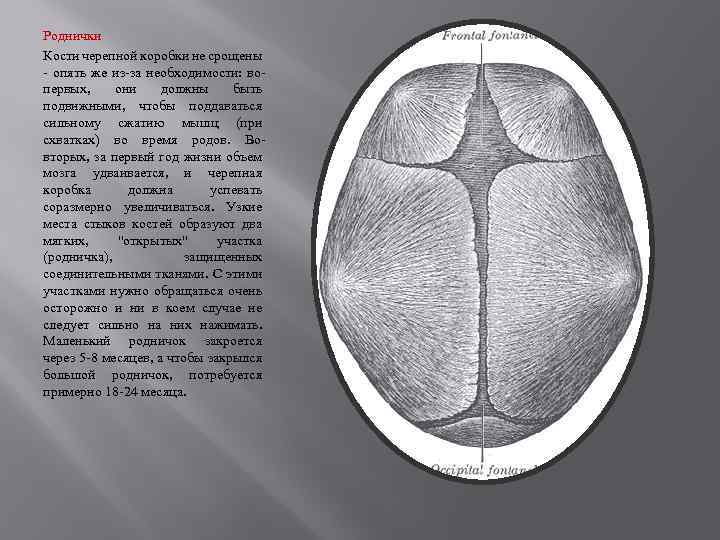

Роднички Кости черепной коробки не срощены - опять же из-за необходимости: вопервых, они должны быть подвижными, чтобы поддаваться сильному сжатию мышц (при схватках) во время родов. Вовторых, за первый год жизни объем мозга удваивается, и черепная коробка должна успевать соразмерно увеличиваться. Узкие места стыков костей образуют два мягких, "открытых" участка (родничка), защищенных соединительными тканями. С этими участками нужно обращаться очень осторожно и ни в коем случае не следует сильно на них нажимать. Маленький родничок закроется через 5 -8 месяцев, а чтобы закрылся большой родничок, потребуется примерно 18 -24 месяца.